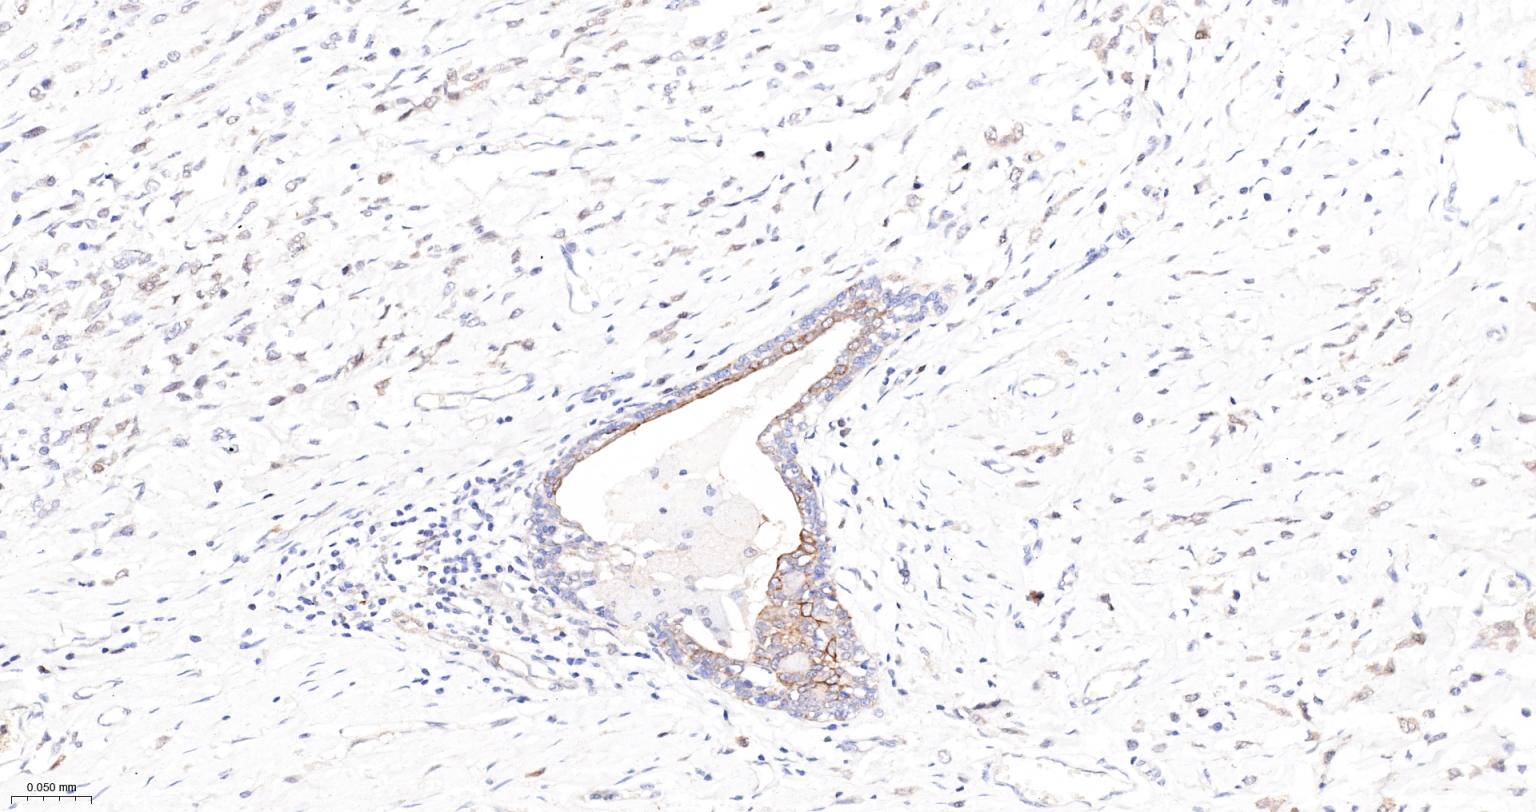

Paraformaldehyde-fixed, paraffin embedded Human Spleen; Antigen retrieval by boiling in sodium citrate buffer (pH6.0) for 15 min; The section was incubated with Cleaved-Caspase 3 p17 Monoclonal Antibody, Unconjugated (bsm-61090R) at 1:200 overnight at 4°C, followed by conjugation to the bs-0295G-HRP and DAB (C-0010) staining.